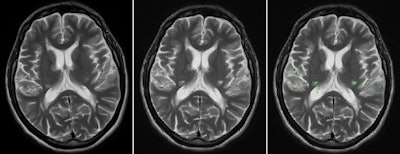

A group led by Varvara Nika from the department of mathematics and statistics at York University in Toronto has developed a software algorithm that automatically performs image registration and calculates any changes between subsequent brain MRI studies. Experimental results with both simulated and real MRI scans show that the software, called EigenBlock Change Detection (EigenBlockCD), outperforms previous methods for detecting changes, according to the researchers.

EigenBlockCD uses principal component analysis to eliminate redundancy and increase computational efficiency, according to the researchers. No preprocessing steps are required, and the algorithm uses blocks of pixels from one scan as training samples to detect changes in the follow-up study.

"The main idea of EigenBlockCD is to perform a local image registration for identifying important structural changes, such as appearance, disappearance, growth, or shrinkage of a lesion, while automatically rejecting unimportant changes due to spatial position of patients, measurement noise, and common imaging acquisition artifacts," Nika told AuntMinnie.com.

In the first step, EigenBlockCD performs an initial global alignment of the images using fixed large radii of blocks of interest. Next, 2D images are aligned by performing a linear transformation of one MR image with its follow-up image via the use of two translation parameters and one rotation parameter. The algorithm then determines any significant changes between the two images by using fixed small blocks of interest.

"The EigenBlockCD algorithm divides the test image into many overlapping blocks," she said. "We assume that voxels from one image will appear again in the follow-up image either at the same location or within a close neighborhood from which the training blocks are learned."

The researchers compared the performance of EigenBlockCD with a simple differencing technique for computing changes between a ground truth image and a changed image. They then repeated the experiment.

In 48 experiments, EigenBlockCD yielded a mean 99.9% correct classification, 75.6% sensitivity (probability that the algorithm detected true changes), and 100% specificity (probability that the algorithm detected nonchanges). In contrast, the simple differencing method achieved 36% correct classification, 32.7% sensitivity, and 100% specificity.